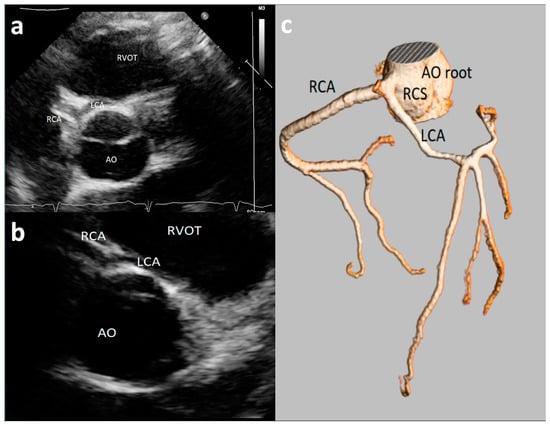

Figure 3. Asymptomatic 17-year-old boy evaluated for the presence of two premature ventricular beats at peak of stress test in routine preparticipation evaluation for sports competition. Parasternal long-axis view showing right coronary artery (RCA) high take-off coronary artery above the sinus of Valsalva (a). The acute angulation origin is clearly visualized in short-axis view (b) and was confirmed at CT (c). After CT confirmation of the defect, a myocardial scintigraphy was performed revealing a small ischemia (8%) in the RCA territory at peak. We advised sport restriction. Ao = aorta, LCA = left common coronary artery, RCA = right coronary artery, LSV = left sinus of Valsalva, RSV = right sinus of Valsalva. (d) is an example of 73-year-old man showing symptoms of dyspnea. 3D-Volume Rendering CCTA showing the right dominant coronary artery (RCA) high take-off two centimeters distal to the sinutubular junction at the level of the anterior ascending aortic wall.

3.6. Coronary Artery High Take-Off

High take-off coronary artery is a rare anomaly [33,34,35,36,37,38,39,40,41,42,43] that may present in isolation or associated with other congenital cardiac malformations [35,36,37,38,39,40,41,42,43], mainly identified for the RCAs (up to 84.46% of cases) [33]. There is still limited literature on the visualization and definition of RCA high take-off by echocardiography [13,14,23]; although there is not a consensus on the definition of high take-off by echocardiography, all the studies included in the present review defined high take-off as an origin above or distal to the sinutubular junction (STJ) [13,14,23]. An example of high take-off of RCA from our case series is reported in Figure 3. A very recent [13] study, of 1045 consecutive elite adolescent football players, identified coronary high take-off origin in 13 subjects (i.e., 1.14%). Eccentric RCA origin with a high take-off and partial intra-arterial course was observed in two cases (with no slit-like ostium and no intramural course); high take-off origin of the RCA with acute angle was observed in one case; high take-off of the RCA origin (with no intramural or slit-like orifice) was observed in 11 cases. Of the latter 11 cases, diagnosis was feasible only from the parasternal long-axis view, where the ostium of the RCA was measured from 2.3 to 6.8 mm above the sinutubular junction [13]. Lytrivi et al. [24] documented RCA high take-off in 53 cases (0.36%), LCA high take-off in four cases, and high take-off of both the coronary arteries in two cases of a valuable cohort of 14,546 pediatric subjects [23].